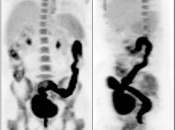

Metformin:

This very popular medication is notorious for causing extensive and extremely intense bowel uptake (colon > small bowel). As this uptake can occasionally limit interpretation, we ask our patients to discontinue Metformin 24-hours prior to their exam.